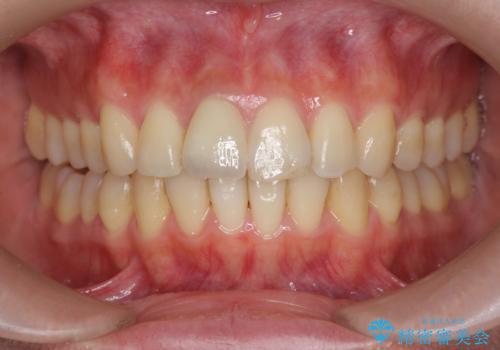

前歯の変色 打撲により失活した前歯の根管・セラミック治療

- 変色してきた前歯の形態回復、色調の改善を求めて来院されました。

X線検査、歯髄(歯の神経)の検査を行ったところ、失活(歯の神経の死んだ状態)であると診断されました。

放置すると変色が進行するだけでなく、根尖病変も形成される恐れが強いことから、根管治療を行ったのちセラミッククラウンによる審美性の改善を計画します。

自然な色調をセラミッククラウンで再現することができ、審美性の改善に大変喜んでいただくことができました。